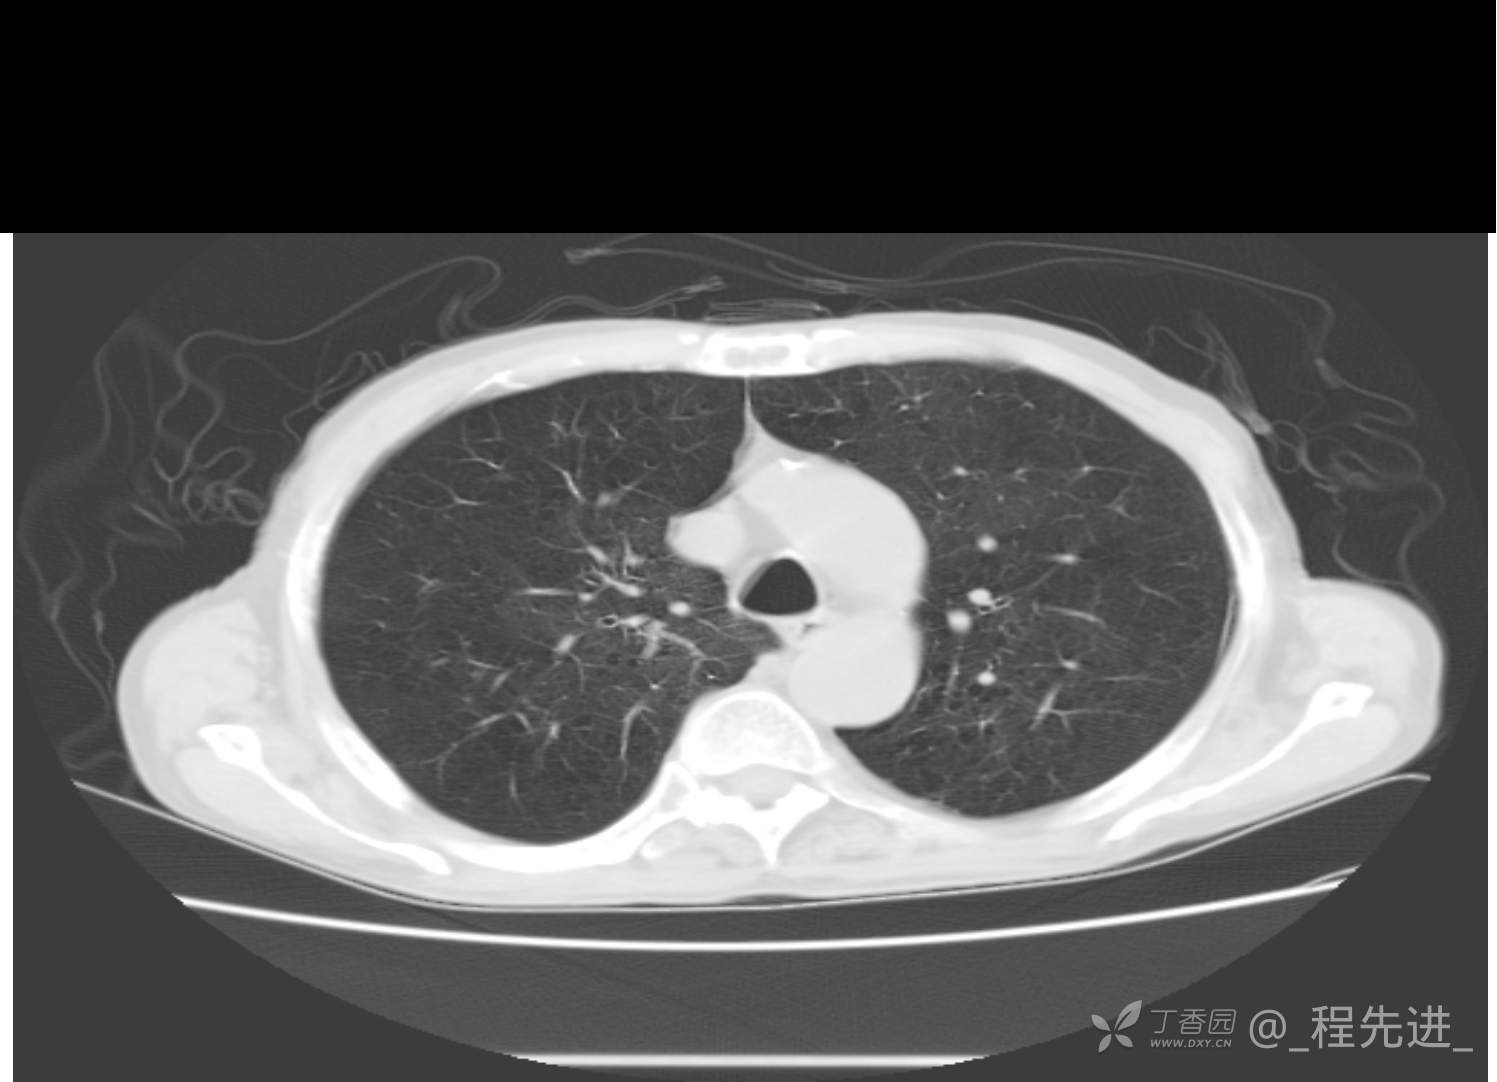

患者性别:男

患者年龄:81岁

简要病史:反复咳嗽、咳痰20余年,加重1周。两肺呼吸音低,可闻及散在干湿啰音。